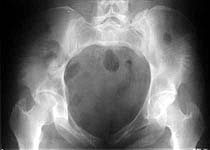

Thank you for the interesting xray images of the anterior/posterior circular pelvic ex fix.

Some images of the subject.